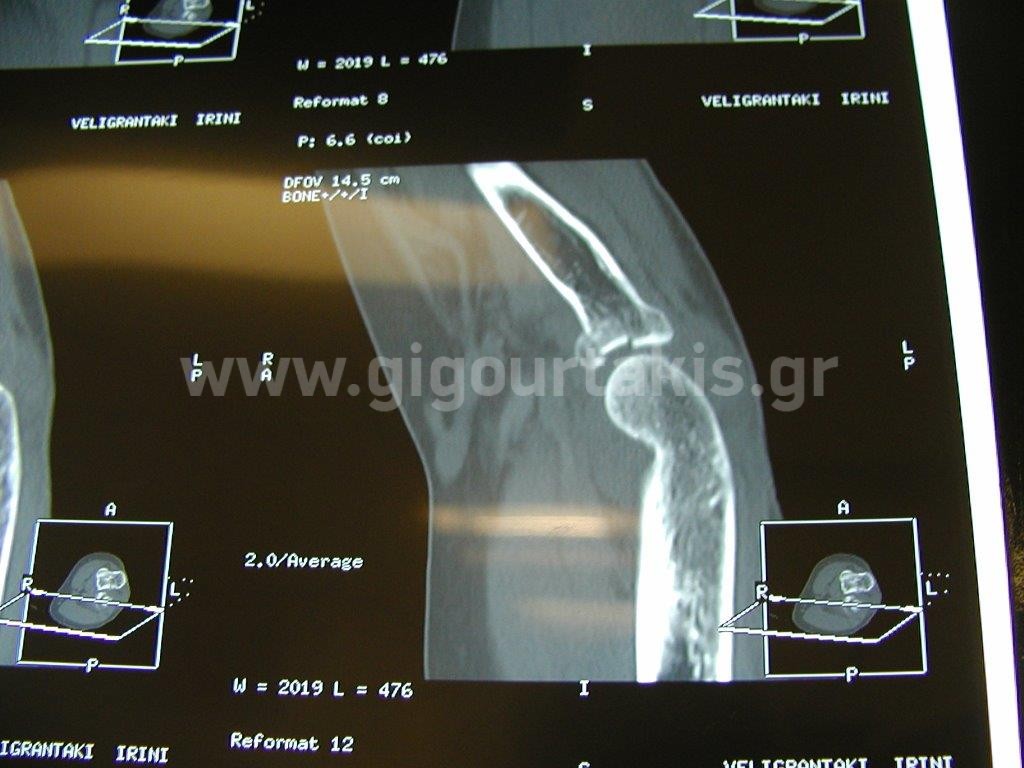

ΚΑΤΑΓΜΑ ΚΕΦΑΛΗΣ ΚΕΡΚΙΔΟΣ ΣΥΝΤΗΡΗΤΙΚΑ ΠΕΡΙΣΤΑΤΙΚΟ 1 01.ΑΡΧΙΚΗ ΚΑΜΨΗ ΑΓΚΩΝΟΣ 02. ΑΡΧΙΚΟΣ ΠΡΗΝΙΣΜΟΣ ΑΝΤΙΒΡΑΧΙΟΥ 03 .ΑΡΧΙΚΟΣ ΥΠΤΙΑΣΜΟΣ ΑΝΤΙΒΡΑΧΙΟΥ 04. ΑΡΧΙΚΗ ΕΚΤΑΣΗ ΑΓΚΩΝΟΣ 05.ΤΕΛΙΚΗ ΕΚΤΑΣΗ ΑΓΚΩΝΟΣ 06.ΤΕΛΙΚΗ ΚΑΜΨΗ ΑΓΚΩΝΟΣ 07. ΤΕΛΙΚΟΣ ΠΡΗΝΙΣΜΟΣ ΑΝΤΙΒΡΑΧΙΟΥ 08. ΤΕΛΙΚΟΣ ΥΠΤΙΑΣΜΟΣ ΑΝΤΙΒΡΑΧΙΟΥ ΠΕΡΙΣΤΑΤΙΚΟ 2 01 02 03 04.ΑΡΧΙΚΗ ΕΚΤΑΣΗ ΑΓΚΩΝΟΣ 05. ΑΡΧΙΚΗ ΚΑΜΨΗ ΑΓΚΩΝΟΣ 06. ΑΡΧΙΚΟΣ ΠΡΗΝΙΣΜΟΣ ΑΝΤΙΒΡΑΧΙΟΥ 07.ΑΡΧΙΚΟΣ ΥΠΤΙΑΣΜΟΣ ΑΝΤΙΒΡΑΧΙΟΥ 08.ΤΕΛΙΚΗ ΚΑΜΨΗ ΑΓΚΩΝΟΣ 09.ΤΕΛΙΚΗ ΕΚΤΑΣΗ ΑΓΚΩΝΟΣ 10.ΤΕΛΙΚΟΣ ΠΡΗΝΙΣΜΟΣ ΑΝΤΙΒΡΑΧΙΟΥ 11. ΤΕΛΙΚΟΣ ΥΠΤΙΑΣΜΟΣ ΑΝΤΙΒΡΑΧΙΟΥ Στις κατηγορίες:ΑΝΩ ΑΚΡΟ, ΣΥΝΤΗΡΗΤΙΚΑ, ΑΓΚΩΝΑΣ ΠΗΧΥΣ, ΚΑΤΑΓΜΑ ΑΓΚΩΝOΣ ΠΗΧEΩΣ, ΚΑΤΑΓΜΑ ΚΕΦΑΛΗΣ ΚΕΡΚΙΔΟΣ